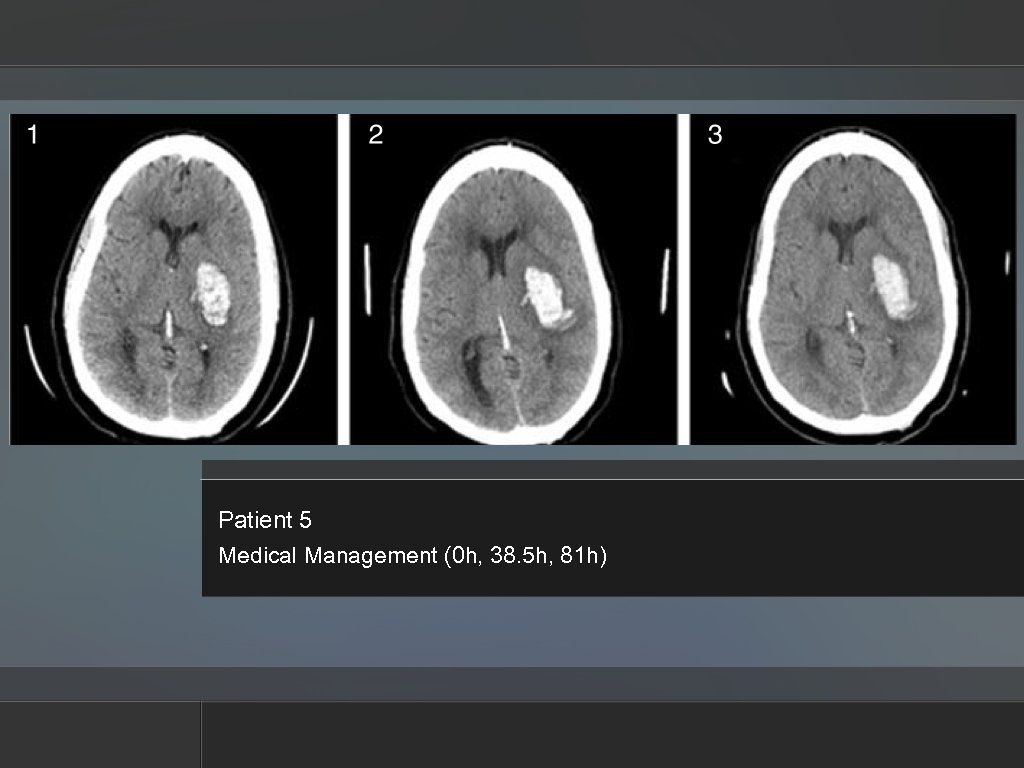

Patient 5 Medical Management (0 h, 38. 5 h, 81 h) Patient 5 Medical Management (0 h, 38. 5 h, 81 h)